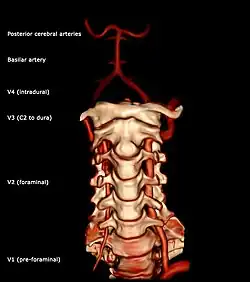

Anatomía

El sistema vertebrobasilar o VBS es el único en la anatomía humana, en que dos arterias diferentes se fusionan en una arteria única. Este sistema arterial provee la circulación del encéfalo posterior.[2]

Las dos arterias vertebrales y la arteria basilar proporcionan sangre a la parte posterior del círculo arterial cerebral y se anastomosa con la parte anterior del círculo, irrigado por las arterias carótidas.